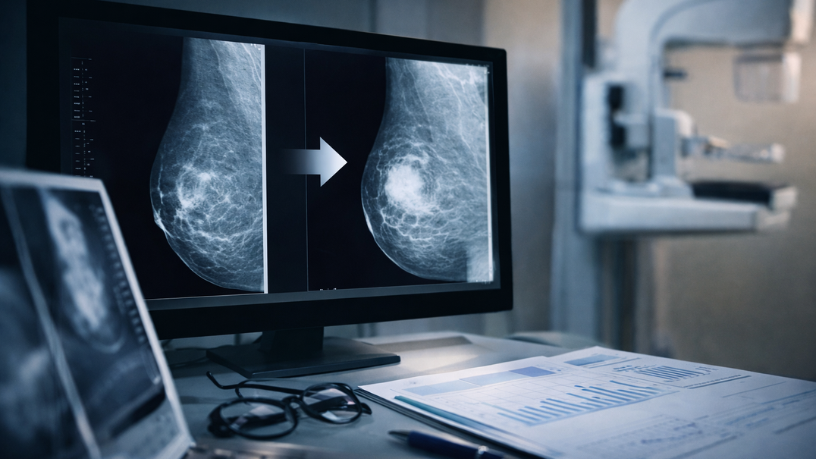

O acompanhamento da saúde das mamas não se limita à realização de um único exame. Vinicius Tadeu Sattin Rodrigues, médico especialista em diagnóstico por imagem, argumenta que a análise evolutiva das imagens obtidas em diferentes momentos é uma das etapas mais importantes da avaliação radiológica. Quando exames são realizados periodicamente, torna-se possível comparar imagens e identificar mudanças no tecido mamário. Esse processo ajuda os especialistas a compreender melhor o comportamento das estruturas mamárias.

A comparação entre exames realizados em momentos diferentes permite observar o comportamento do tecido mamário ao longo dos anos. O doutor Vinicius Tadeu Sattin Rodrigues explica que essa análise evolutiva ajuda a identificar mudanças estruturais que podem ocorrer de forma gradual. Pequenas alterações podem se tornar mais evidentes quando o especialista compara imagens antigas com as mais recentes.

Além disso, a comparação permite confirmar a estabilidade de determinadas estruturas presentes nas mamas. Quando uma formação aparece da mesma maneira em exames anteriores, isso pode indicar que ela faz parte da estrutura natural do tecido mamário. Nesse contexto, o histórico de exames se torna uma ferramenta importante para a avaliação clínica.

Durante a análise comparativa, o especialista observa diferentes características das imagens. Entre os elementos avaliados estão a presença de nódulos, alterações de densidade e pequenas calcificações no tecido mamário. Segundo Vinicius Tadeu Sattin Rodrigues, essas características ajudam a compreender melhor a evolução das estruturas mamárias.

A observação cuidadosa permite identificar mudanças que poderiam passar despercebidas em exames isolados. Desse modo, a comparação entre imagens amplia a capacidade de investigação. A análise detalhada contribui para decisões médicas mais fundamentadas.